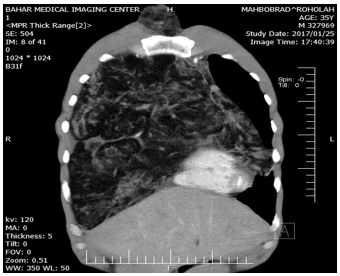

Figure 3: Showing Sagittal CT scan of chest(in another window) showing a mass to occupying total right hemithorax and and extend to left hemithorax and neck with strands and islands of soft fatty tissue.

Haematological and serological investigations, including tumor markers (alphafetoprotein, lactate dehydrogenase, beta human chorionic gonadotrophin, and alkaline phosphatase) were normal and not contributory to the diagnosis. With these radiologist report, the patient underwent to US-needle biopsy identified atypical cell and suspicious to liposarcoma. On completion of the preoperative evaluation, a right extensive posterolateral thoracotomy was performed via the fifth intercostal space. a large, encapsulated, vaguely lobulated mass was found within the anterior mediastinum. The mass arose in the anterior mediastinal fat, increasing in size as it extended above to the right side of neck and to the superior vena cava to the right inferior pulmonary vein, and extended to left hemithorax, compress the heart, diaphragm and shifted the mediastinum to the left, The mass occupied approximately 90% of right and 30% of left pleural cavity, resulted in marked compression and totally collapsed of right lung and partially collapse of left upper lobe (Figure1-4).